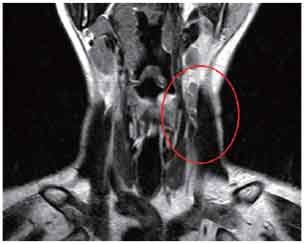

MRI-Ultrasound Fusion in Transperineal Prostate Biopsy

Bi-planar MRI-Ultrasound real-time fusion

3D navigation and tracking